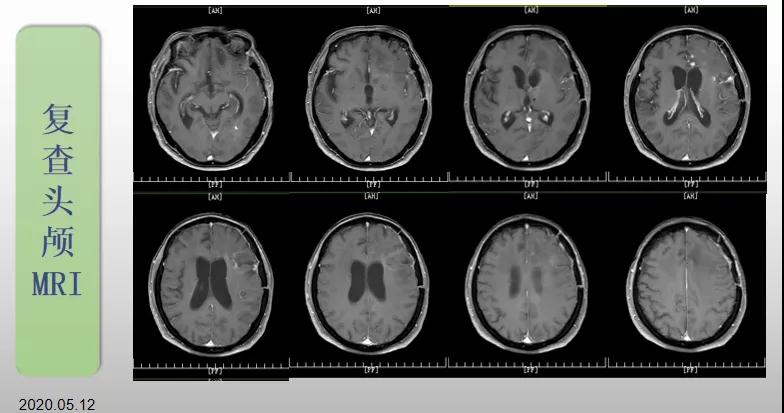

綜合治療 電場治療助70歲患者回歸正常生活

70歲的郝女士去年曾在外院查出“左額島葉”膠質(zhì)母細胞瘤(WHO Ⅳ級),并做了左側(cè)額島葉占位性病變切除術(shù)。術(shù)后進行了同步放化療。由于治療條件有限,郝女士慕名來到我院就診。賀世明主任率領(lǐng)醫(yī)護團隊立即為郝女士進行了全面的檢查,決定為其進行綜合治療 電場治療。經(jīng)過三個多月的綜合治療,患者復(fù)查頭顱MRI病變較前明顯縮小。出院時,郝女士神志清醒,睡眠飲食正常,說話很流利?!拔沂翘芍M來的,現(xiàn)在不用人攙扶,自己就可以走出病房了?!焙屡坷t(yī)護人員的手說。